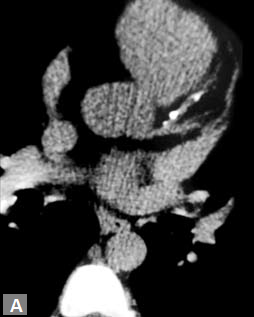

Aorta11 has five segments namely: (1) root, (2) ascending aorta, (3) proximal aortic arch, (4) distal aortic arch and (5) descending thoracic aorta. Size and shape of aorta vary among individuals and with age in an individual. Aortic root includes annulus, valve and sinuses of Valsalva. Average diameter at the level of sinotubular junction is 36 mm. Ascending aorta extends from sinotubular junction to the level of origin of innominate artery. Average diameter in adult is 35 mm. The aortic arch extends from the origin of right innominate artery to origin of left subclavian artery. Isthmus extends from left subclavian artery to the level of ligamentum arteriosum and is slightly narrower than adjoining descending thoracic aorta, particularly in infants. Most cranial part of descending thoracic aorta is more prominent than rest of descending thoracic aorta and is known as aortic spindle, more commonly appreciated in children. Average luminal caliber of mid thoracic aorta is 25 mm. Distal descending thoracic aorta just above diaphragm has an average of 24 mm.

Connective tissue disease, hypertension and iatrogenic (Figs 19K to L) injury are the common causes for dissection. Radiologist not only establishes the diagnosis, also evaluates the extent of dissection, presence of thrombosis particularly in false lumen. In case of type A dissection, involvement of aortic root is determined. Relation of thrombosed lumen and ostia of coronary vessels, cephalad branches (Figs 19N, R to V) of aorta is determined. Most of the occasions membrane is demonstrated. Spiral nature of the membrane can be seen

by evaluating the aorta in all the three orthogonal planes

(Figs 19O to R).

Tennis ball sign is the classical appearance of dissection on

transverse section.

Double barrel appearance is seen on coronal and sagittal

images. Type B dissections can extend even to common

iliac arteries bilaterally. Superiorly it can extend to involve

common carotid and vertebral arteries.

Second dissection within the true lumen causes “Benz”

sign (Fig. 19J).